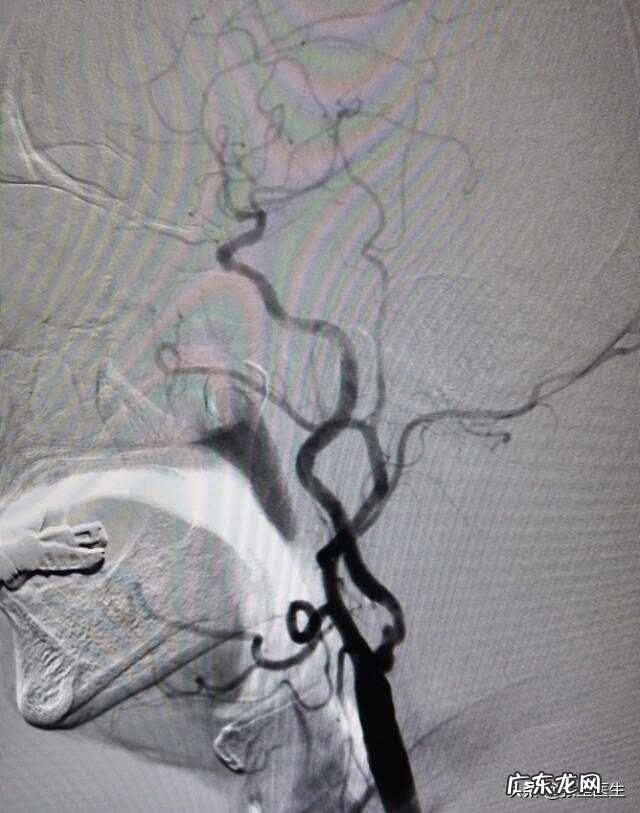

①大家请注意 ,我们大脑的血供是来自于动脉,而人体支配大脑血液一共可分为两套系统 。即颈内动脉系统、椎-基底动脉系统 。其中颈内动脉系统供应的是我们颅内前3/5的结构;而椎-基底动脉系统供应的则是枕叶、脑干、小脑、颞叶、脊髓前段等后2/5的结构 。

②当大家理解了大脑血供的来源后我们再来看看动脉硬化有什么后果,通俗点讲也就是说动脉硬化后动脉的弹性就降低 。随着时间的进展,慢慢的就会出现粥样斑块,进而引起血管狭窄,血黏度升高,微血栓形成 。大家不妨想一想,本来供应大脑的血管是比较粗的,现在因为动脉粥样硬化血管变狭窄了,那大脑是不是供血就不足了 。

①这里就涉及到我上面所讲的第二套供给大脑血液的动脉系统,即椎-基底动脉系统 。前面我也介绍过像脑干、小脑、颞叶、脊髓前段、颅神经等血供主要来自于椎动脉供给 。而从解剖学来看,椎动脉从锁骨上动脉分支后会顺颈椎横突孔上行,这一段呢刚好有横突孔保护,所以不容易受压 。

②但是请注意,因为椎动脉只有从横突孔才可进入颅内段,所以像环枕筋狭窄、环枢关节错位、颈椎间盘脱出等就容易引起椎动脉受压 。椎动脉受压有什么后果不言而喻,故而造成这种类型的脑供血不足的主要原因为颈椎病的环枕筋狭窄及环枢关节错位引起的椎动脉型及交感神经型颈椎病 。